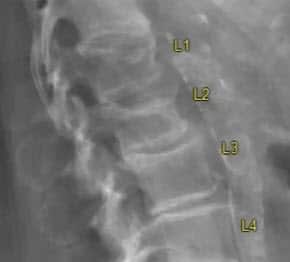

Fractures are often the first sign of the disease for people living with osteoporosis, and vertebral fractures are among the most frequent type. Why does this happen? “The static and dynamic load which the spine is subjected to is much higher than the one of other bone segments. The spinal segment most frequently affected by compression fractures is the lumbar one, in the lower back region, due to its higher static and dynamic load. Also, the last two thoracic vertebrae, in the mid-back region, are frequently a fracture target because of higher dynamic load, consequent to spinal torsion, flexion, and extension,” Dr. Stafa clarifies.

For some patients with more severe osteoporosis, Dr. Stafa shares that “the mid thoracic vertebrae can also fracture.” He advises giving special attention to the sacrum, that sits below the lumbar vertebrae, which frequently has underdiagnosed fractures. “Compression fractures of the cervical spine in the neck region and of the upper thoracic region are rare,” Dr. Stafa adds.